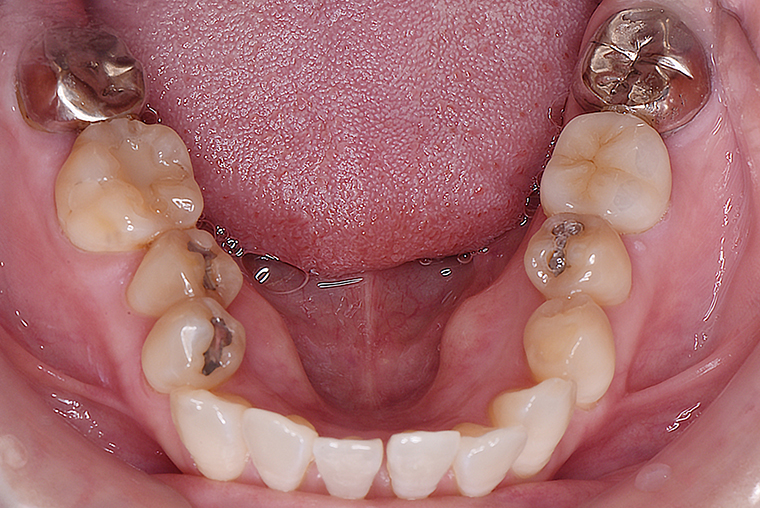

Case Study53歳女性ガタガタな歯のマウスピース矯正-矯正期間1年4ヶ月

BEFORE

AFTER

矯正で、逆の噛み合わせと全体的な歯のデコボコを治したいと思い、治療を始めました。

年齢的に迷いもありましたが、しっかり説明していただけたので安心して進められました。

矯正後は反対の噛み合わせもきれいに整い、見た目もすっきりしました。